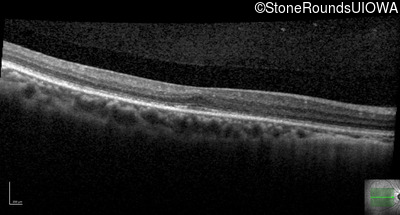

Optical Coherence Tomography - Left - 20/30 +2

Exemplar / OCT Stack